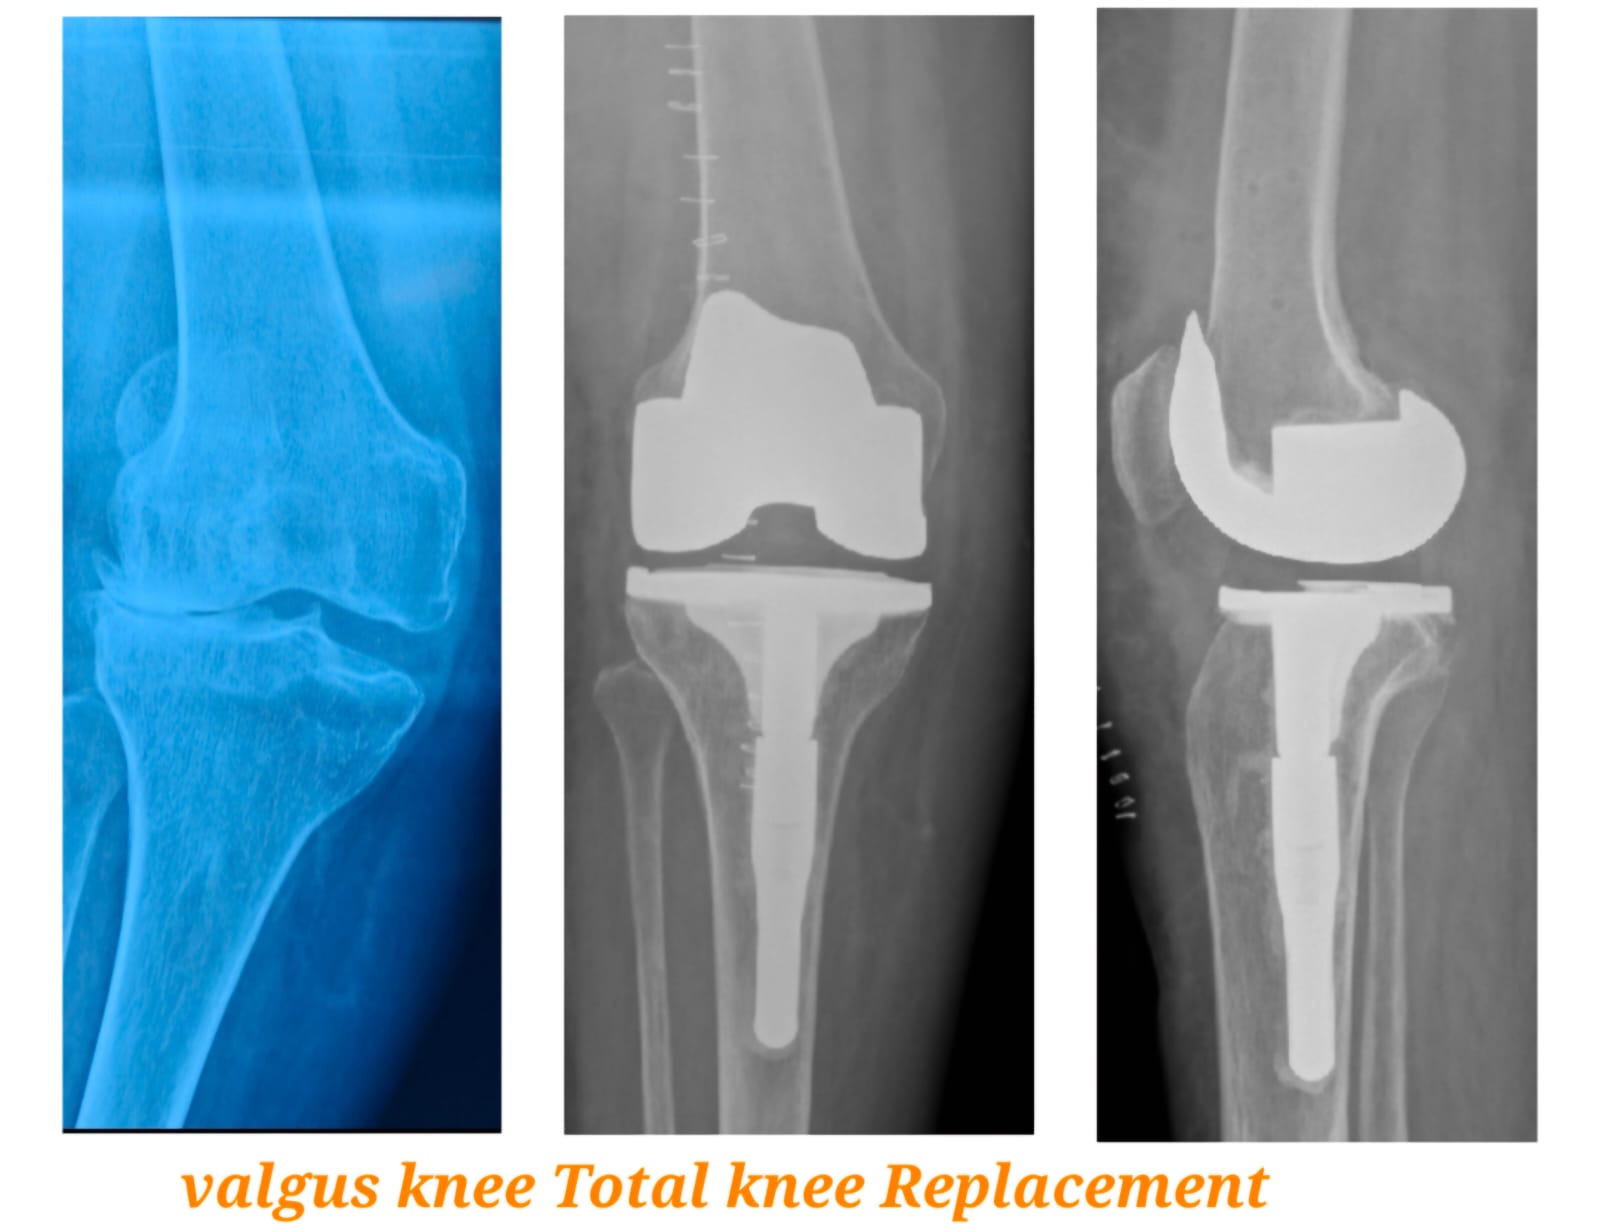

Knee replacement, also known as knee arthroplasty, is a surgical procedure performed to relieve chronic knee pain and restore joint function in patients suffering from advanced arthritis, severe joint damage, or deformities. The procedure involves replacing damaged cartilage and bone surfaces with durable artificial implants that restore smooth knee movement.

Knee arthroplasty is carefully planned based on the patient’s age, activity level, degree of joint damage, and overall health. Modern surgical techniques and advanced implant designs allow improved alignment, stability, and long-lasting outcomes with reduced postoperative discomfort.